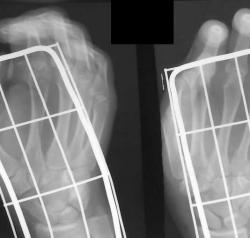

В связи с появлением и широкой популярностью шлифмашинок (в просторечии болгарки), травмы нанесенные этими прогрессивными агрегатами стали широко распространены. Характерной их особенностью являются переломы в виде линейных дефектов или ампутаций, чаще кистей-предплечий, стоп-голеней. Вот характерное наблюдение.

Изображение